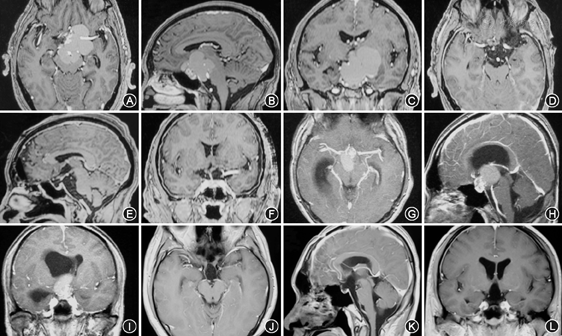

根据术者术中判断及术后影像学判定肿瘤切除程度(图1,图2)。本组病例肿瘤全切除124例(73.4%),次全切32例(18.9%),大部分切除13例(7.7%)。169例患者临床资料见表1。本组无手术相关死亡病例,术后住院8~85 d,平均17.3 d。垂体柄完整保留104例,部分保留21例,垂体柄与肿瘤一起切除21例,术中未见垂体柄23例。5例选择前纵裂入路术中切断前交通动脉,术后无不良反应。6例巨大颅咽管(最大径>6 cm)在术中磁共振辅助下手术,其中4例全切除,2例次全切除。

所有患者术前均行头颅MRI平扫及加强扫描,126例行CT检查。头颅CT有明确钙化的73例。肿瘤大多数位于鞍上,中线生长,压迫视神经及视交叉,向上生长进入三脑室内,部分肿瘤可突入脚间池内,少部分肿瘤向侧方生长甚至突入侧脑室内。室间孔或中脑导水管阻塞者可出现幕上脑室扩大,合并中度至重度脑积水患者28例。肿瘤最大径1.5~7.8 cm。囊性23例,囊实性125例,实质性21例。增强扫描肿瘤囊壁和实质性部分有明显强化。肿瘤主体位于鞍内17例,主体位于鞍上未侵及三脑室的51例,主体位于鞍上侵及三脑室内外的95例,其中进入侧脑室的5例。完全在第三脑室内6例。